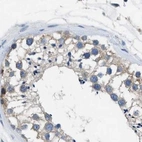

Immunohistochemical staining of human cerebral cortex, endometrium, fallopian tube and testis using Anti-PGR antibody HPA017176 (A) shows similar protein distribution across tissues to independent antibody HPA004751 (B).